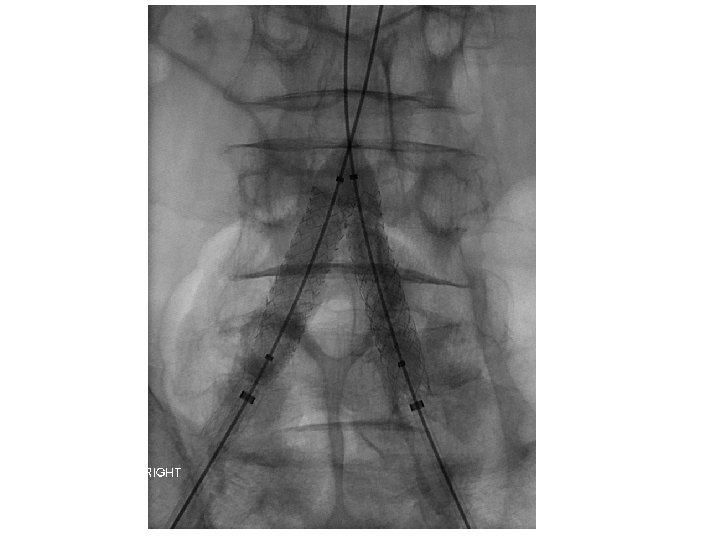

SE Stent Compression Is A Problem • 53 patients (28 females) prospective aorto-iliac stent • 165 aorto-iliac stents placed with CBCT confirmation • 20/53 patients underwent adjunctive procedures after the primary stenting • In 24. 5% (13/53) cases, adjunctive procedures were indicated solely on the CBCT findings • 26 of the 53 patients had kissing stents placed at the aortic bifurcation • Of the kissing stent patients, 34. 6% required adjunctive procedures and in two thirds these stent compressions were detected only by CBCT. Törnqvist P, et al. Utility of Intra-operative Cone Beam Computed Tomography in Endovascular Treatment of Aorto-iliac Occlusive Disease. Eur J Vasc Endovasc Surg. 2015

Kissing SE Stents Often Asymmetric Subgroup analysis between the types of stents used and adjunctive procedure showed that self expandable stents were more prone to need adjunctive procedure in the common iliac artery (p =. 048) Törnqvist P, et al. Utility of Intra-operative Cone Beam Computed Tomography in Endovascular Treatment of Aorto-iliac Occlusive Disease. Eur J Vasc Endovasc Surg. 2015